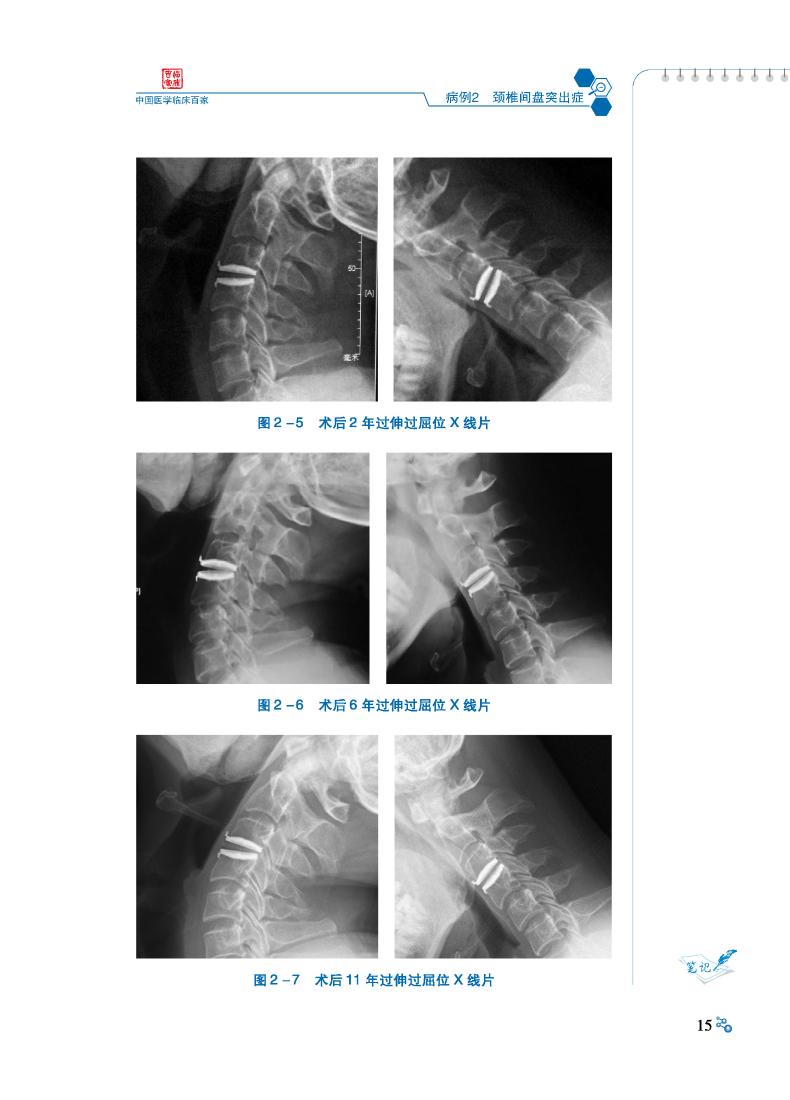

病例2 颈椎间盘突出症